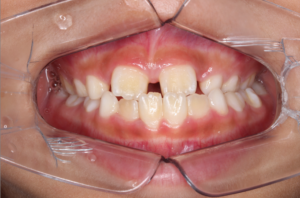

After |

反対咬合(受け口)の治療のためムーシールドと呼ばれるマウスピース型の機能的顎矯正装置を使って改善したあと、

急速拡大装置とマウスピース矯正装置を使用して治療を行っています。

| 主訴 |

反対咬合(受け口) |

| 年齢 |

10歳 男性 |

| 治療期間 |

1年6ヶ月経過(治療継続中) |

| 治療費 |

¥450,000(税別) |

After